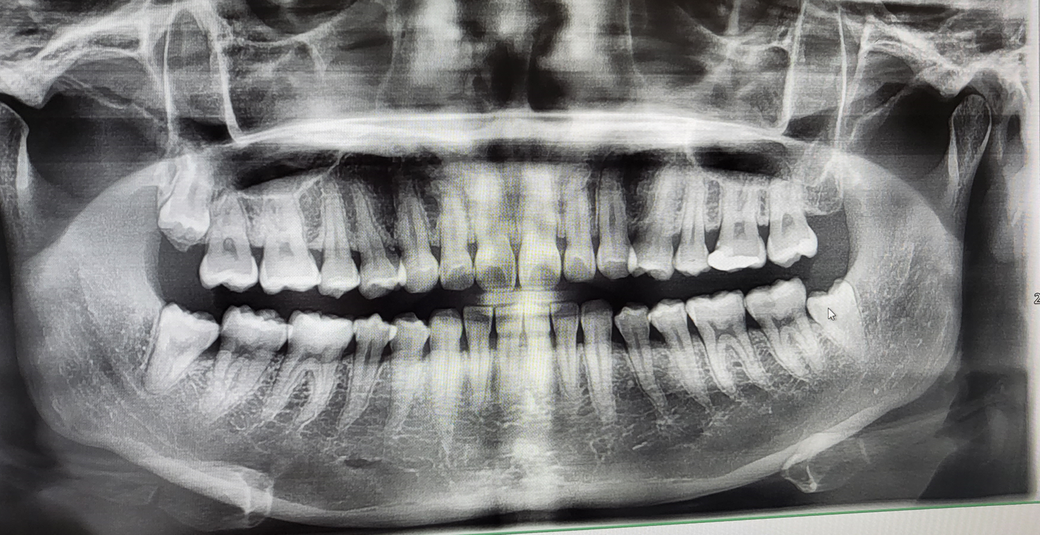

예방법이나 다른 방법이 없는지요... 사진은 사랑니 발치 전 사진입니다 (오른쪽 아래 사랑니 발치하였습니다)

• 1번 째 사진